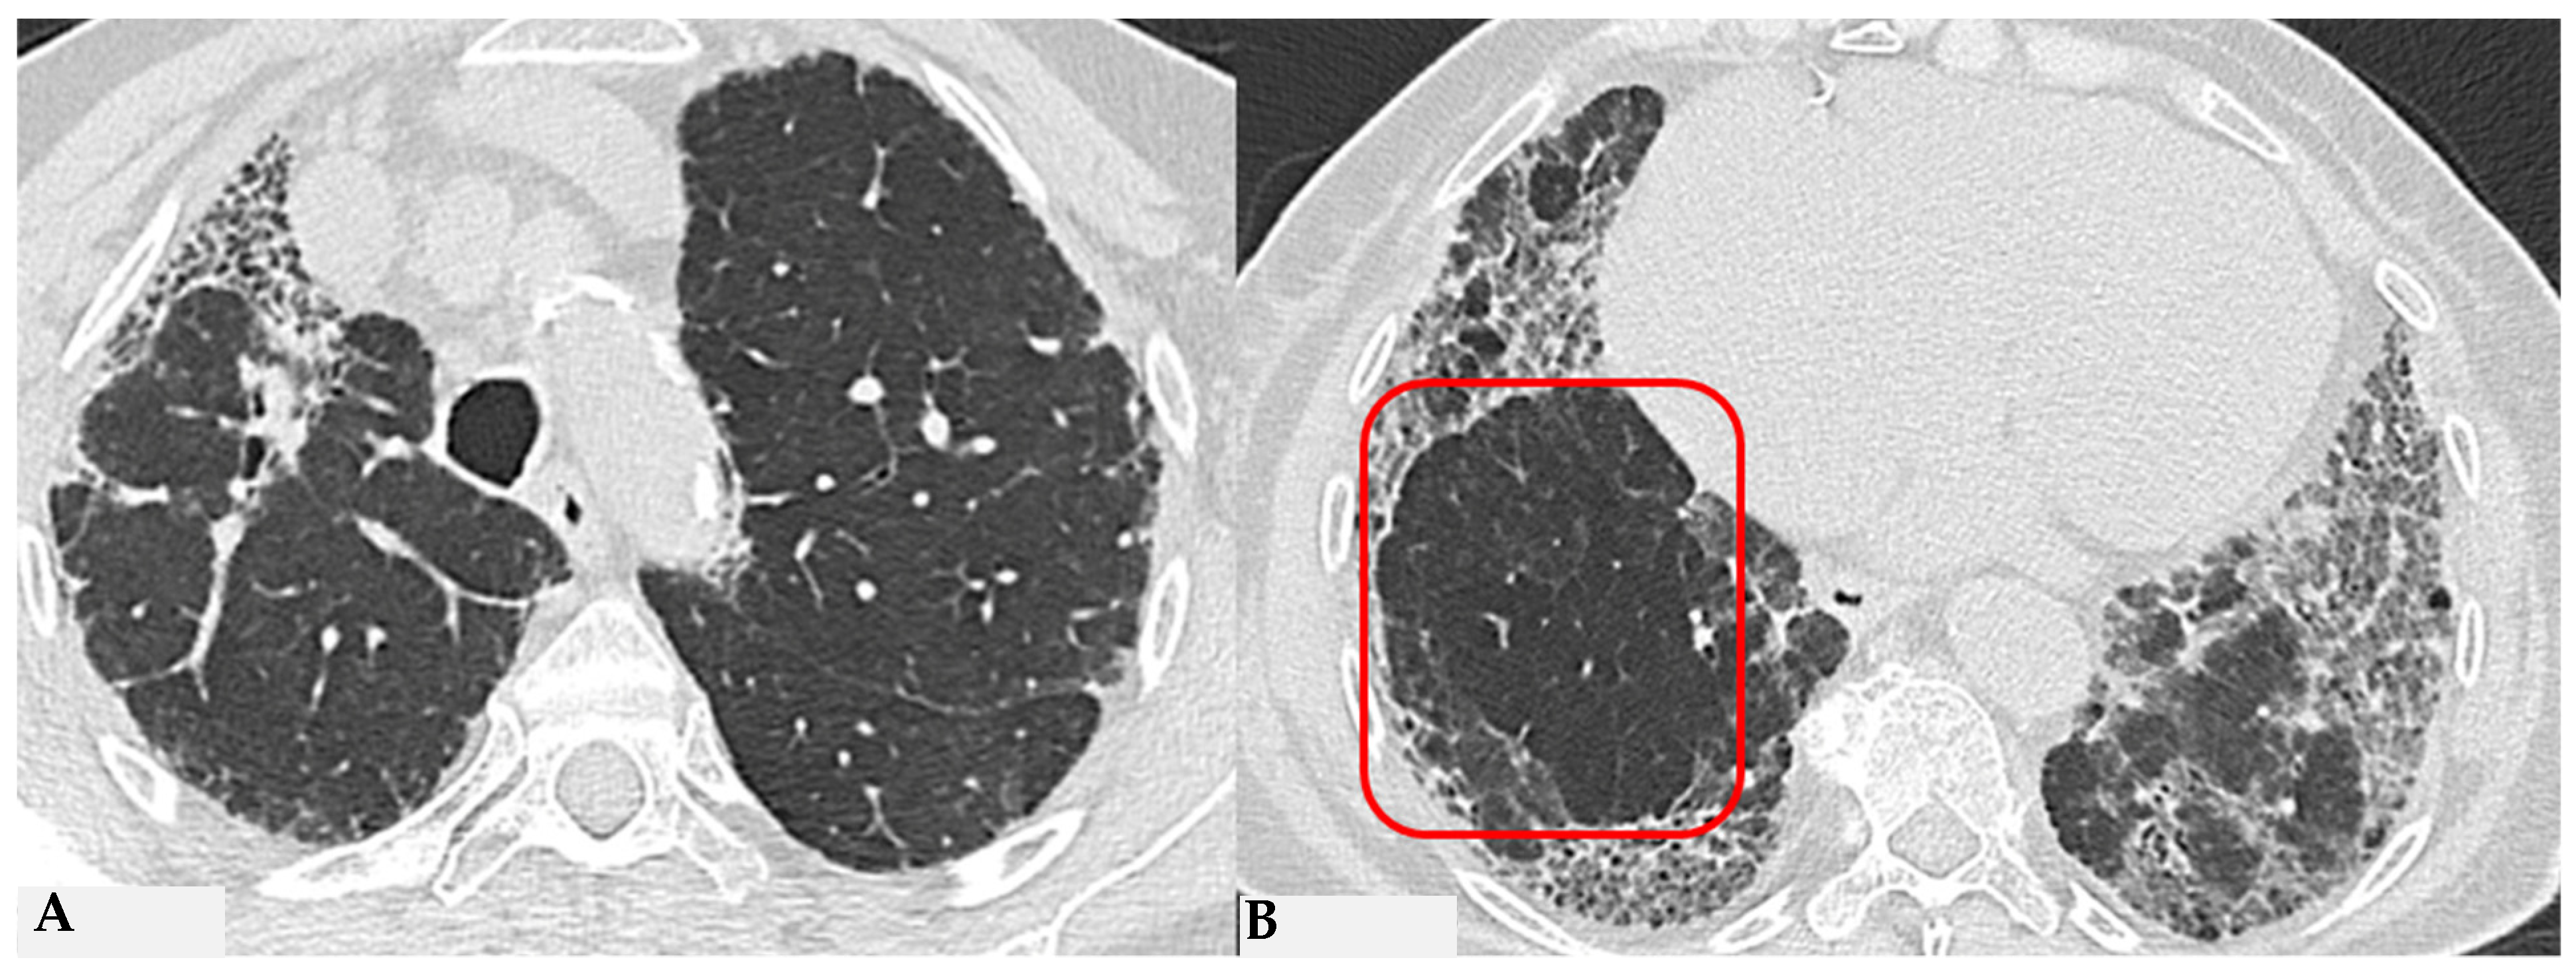

Figure 9.

Truly indeterminate HP pattern. Chest HRCT, axial scan HRCT pattern characterized by mild fibrotic changes of a limited extent with patchy GGO in the upper lobes (A); the lower lobes show GGO, fine reticulations with modest mosaic attenuation and rare traction bronchiectasis/bronchiolectasis (B) with a “truly indeterminate” pattern according to new HP guidelines (2020) [4].

Figure 10.

f-NSIP pattern: chest HRCT, axial scan. Mild fibrotic changes of limited extent with a greater distribution in the upper lobes with superimposed GGO (A); the lower lobes show marked extension of GGO, fine reticulations with traction bronchiectasis/bronchiolectasis (B); “fibrotic NSIP pattern” according to new HP guidelines (2020) [4].